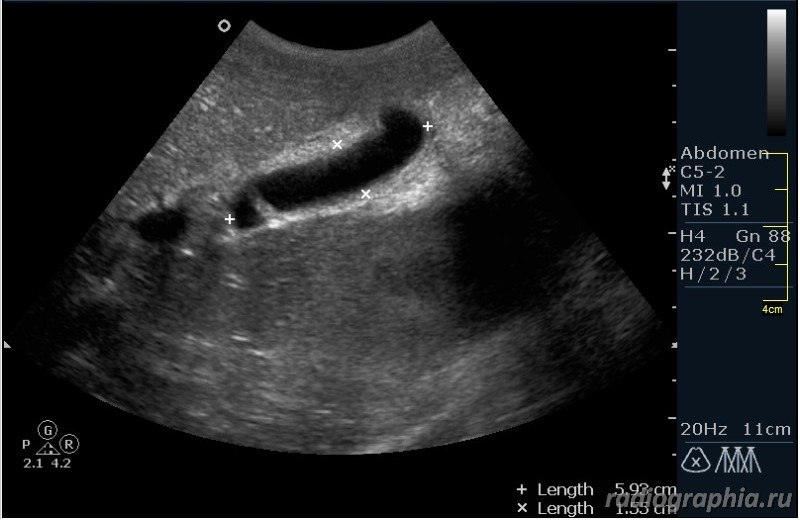

Как вы думаете, при какой патологии можно наблюдать такую сонографическую картину?

Похоже на расширенные внутрипеченочные протоки ,отек стенок ж.пузыря--может быть при остром гепатите

Гепатиты - такой ответ автор считает верным.